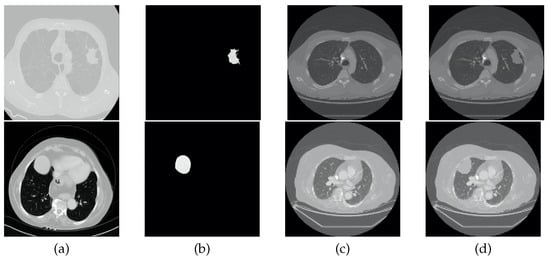

- Including the lung nodules, which, in the majority of cases, appear as a well defined higher density area. Peripheral lung nodules constitute a harder group of nodules to define and, in this case, the key factors were to evaluate the different densities between the chest wall and the nodule, as well to find the fine well-defined line that characterizes the pleura.